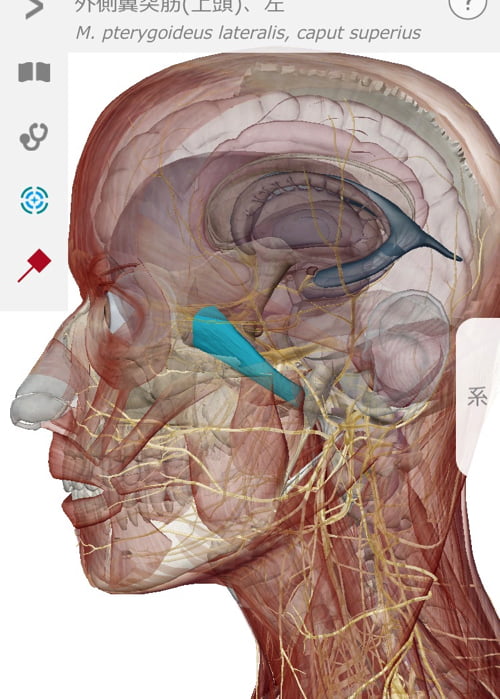

視神経が過敏になっていくのと同時に

目に関わる筋肉や水晶体・首や肩の筋肉なども固まっていきます。

仕事などで目を酷使すると視神経が過敏になって関連する筋肉が硬直。

最後に視神経のルートを辿りながら筋肉や頭骨の微調整をして終了です。